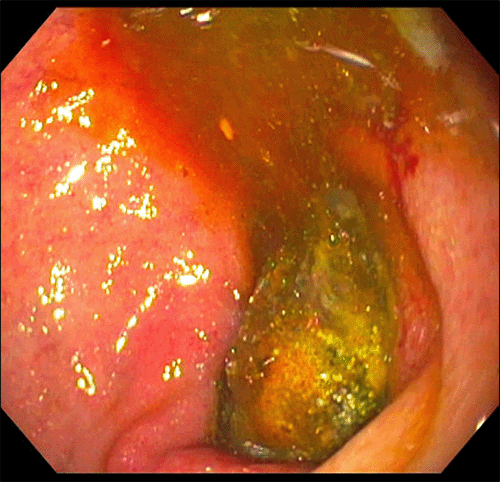

Figure 3. Endoscopic Identification of Duodenal Gallstone. Published with Permission

Gallstone impacted within the second portion of the duodenum, as identified via upper endoscopy